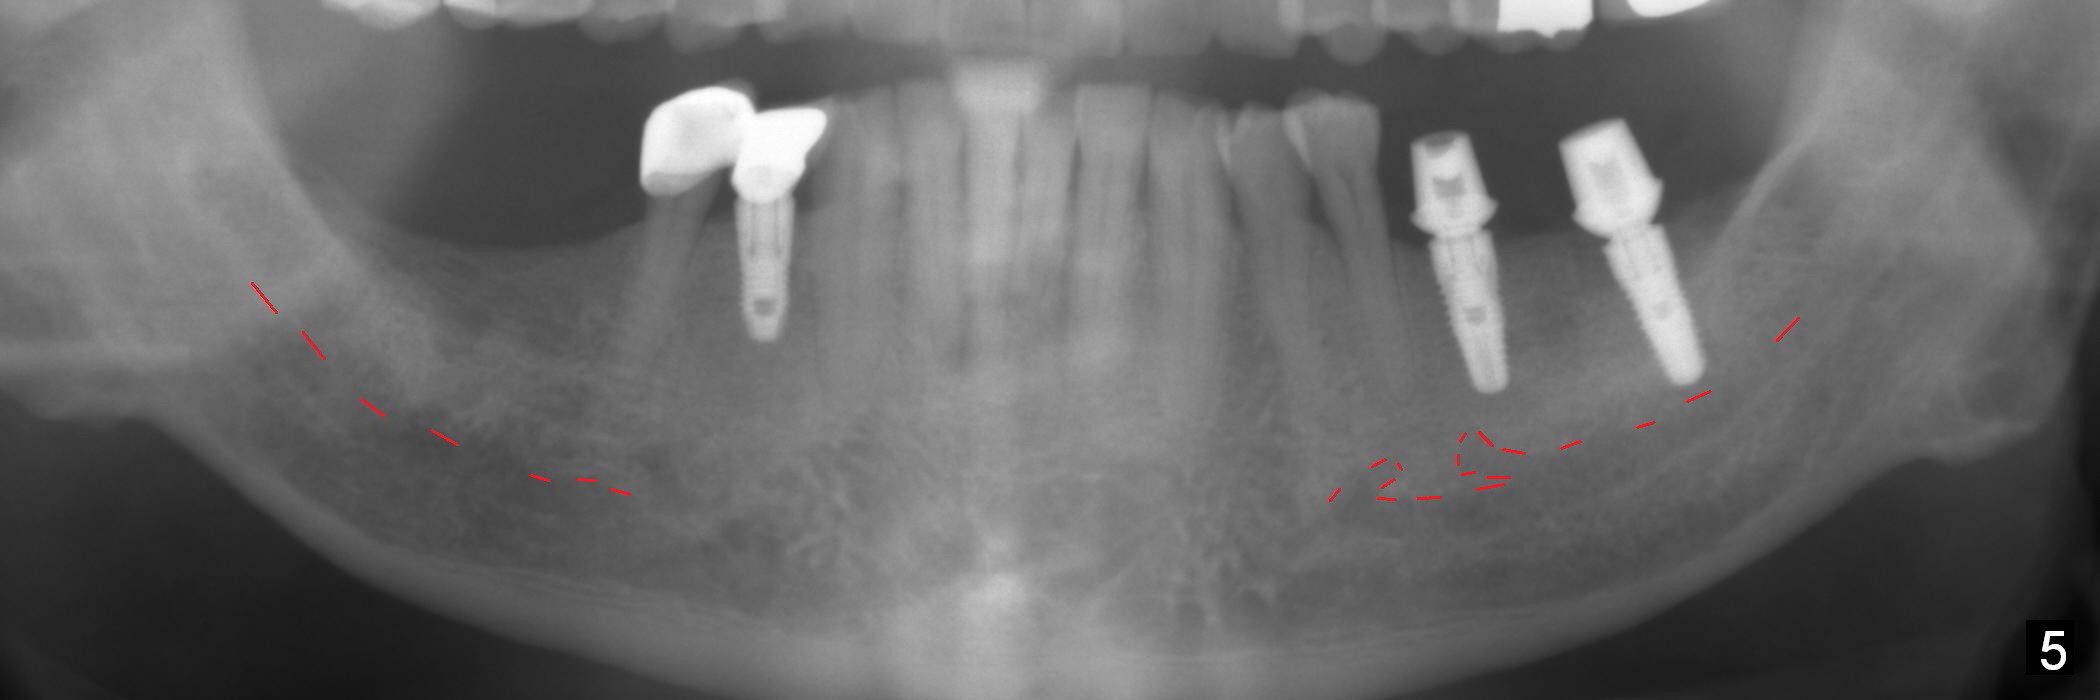

A 64-year-old man has lost 4 molars (Fig.1 posterior view of mounted casts) and is eager to have them back. Implants will be placed at #18 and 19 first (Fig.2). Use surgical stent and starter drill to initiate osteotomies through the gingiva. An incision will be made next. Adjust buccolingual position of the osteotomies. Depth will be 10 and 12 mm at #18 and 19, respectively. Take postop panoramic X-ray for #30 and 31 implant design.

In fact, initial depth for #18 and 19 is 12 mm, quite close to the Inferior Alveolar Canal at #18 (Fig.3 (red dashed line: the superior border of the former). By mistake, the implant at #18 is placed a little deeper than necessary, since the buccal bone is inferior to the lingual one (Fig.4; 5.3x12 mm vs. 5.0x12 mm for #19). As planned, panoramic X-ray is taken immediately postop. Bone height at the 2nd molar decreases drastically as compared to that of the 1st molar, especially on the right side (Fig.5 (abutments: 6.8x5(2) mm for #19, 7.8x5(3) for #18, respectively)). For #30,31 implant placement, initial depth will be 10 and 8 mm, respectively. Follow it faithfully. The implant at #31 could be as large as 5.9 or 6.4 mm to compensate for the length.